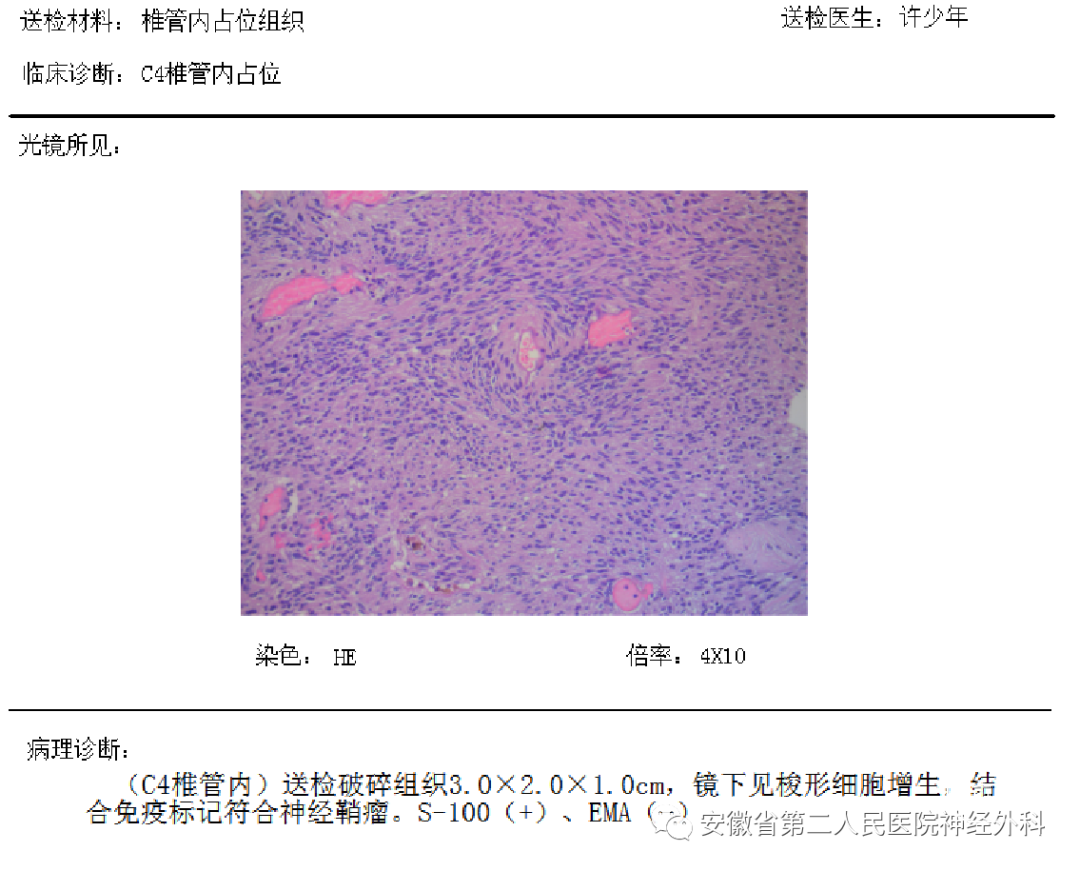

术后病理:神经鞘瘤